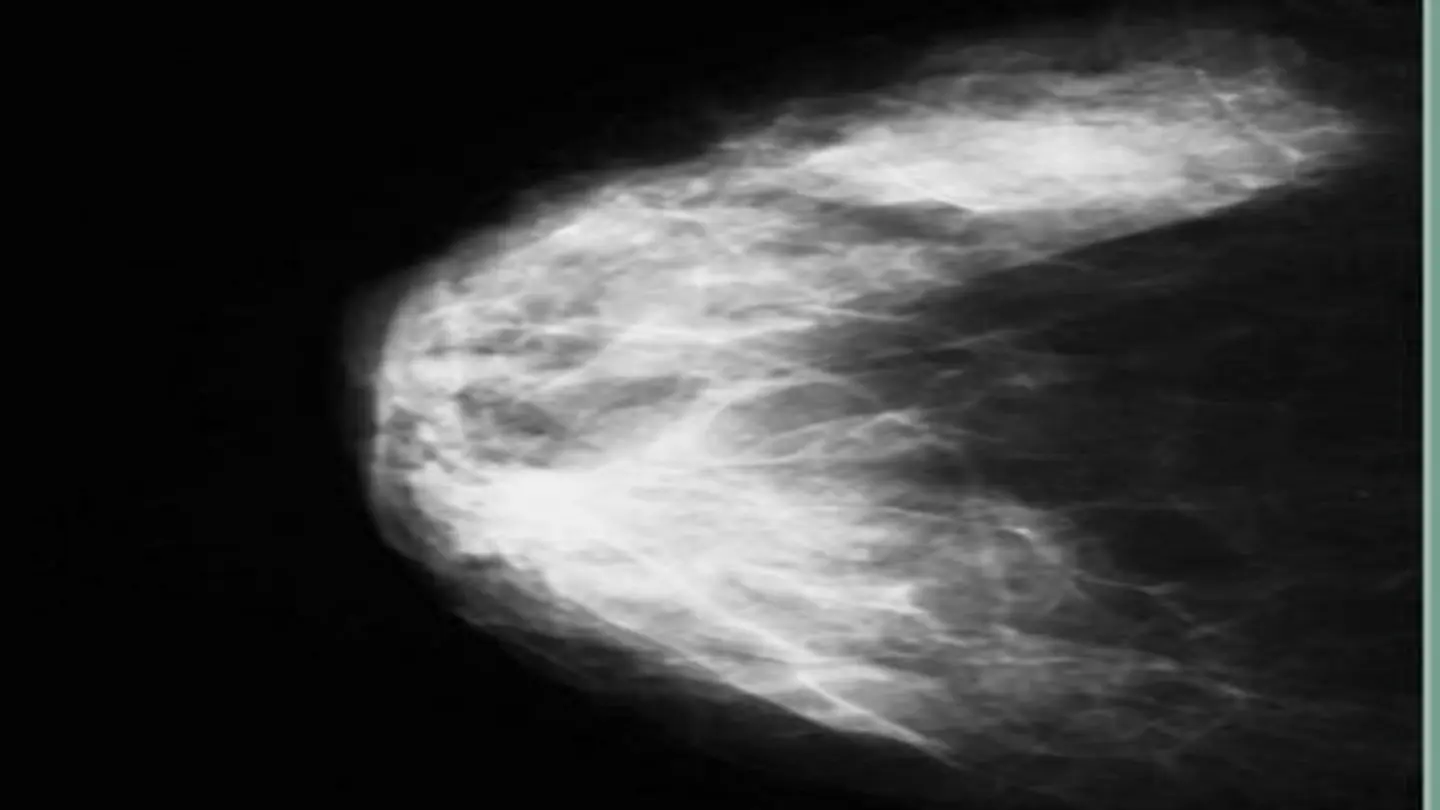

Breasts are composed of fatty tissue, fibrous tissue, and glandular tissue. The density of breast tissue refers to the relative amounts of these components. Women with dense breasts have more fibrous and glandular tissue, which appears white on a mammogram, similar to cancerous tumors. This can make it challenging for radiologists to distinguish between normal dense tissue and potential cancerous growths. Breast density is typically determined through a mammogram and categorized into four levels: almost entirely fatty, scattered areas of fibroglandular density, heterogeneously dense, and extremely dense.

Studies have shown that women with dense breasts have a higher risk of developing breast cancer compared to women with less dense breasts. The exact reasons for this increased risk are still being investigated, but it is believed that dense tissue may provide a more favorable environment for cancer cells to grow. Additionally, the masking effect of dense tissue on mammograms can delay the detection of tumors, potentially leading to later-stage diagnoses.